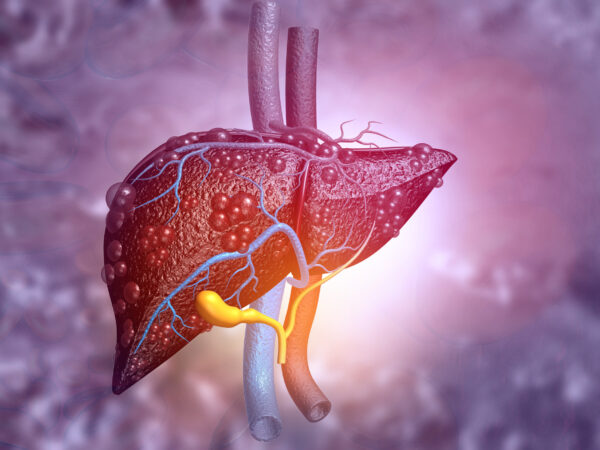

A milestone achievement: 3,000 patients have joined the NAFLD BioResource

On 18th October 2022, the National Institute for Health and Care Research (NIHR) Birmingham Biomedical Research